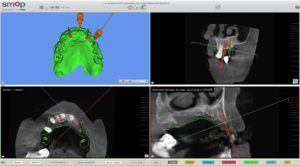

Un cone beam et une prise d’empreinte optique ont été nécessaire pour réaliser la planification implantaire du cas.

Il a été prévu de poser 6 implants au Maxillaire et 4 implants à la mandibule .

2 guides SMOP ont été imprimé, appuis dentaires, muqueux + fixation par clavettes.